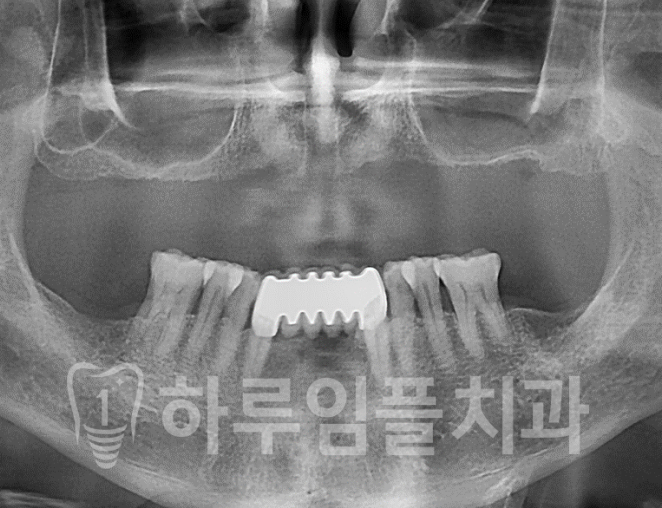

올온엑스 case

상악의 치아가 하나 없으시죠?

오랜 기간 틀니를 사용하고 계셨는데,

잇몸뼈 흡수가 심하고,

위쪽 잇몸이 심하게 후퇴되어 있는

상태셨습니다.

즉, 임플란트를 많이 심고 싶어도

심을 뼈가 충분하지 않습니다.

이런 경우가 위에서 설명드린 올온엑스에

적응증이라 할 수 있습니다.